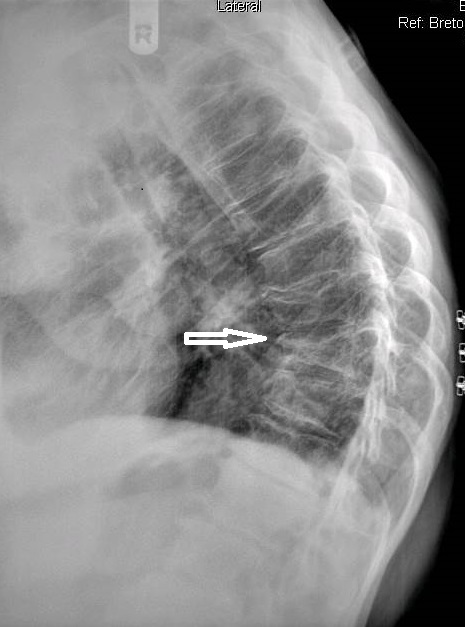

On figure 1, the original AP thoracic projection, an oval density is seen in the periphery of the right lung field (white arrow points to lesion). A thoracic and lumbar scoliosis is also seen. The lateral projection revealed multilevel degenerative change, as well as compression fractures at T9 and T10, with a focal kyphotic deformity seen in figure 2. Since a PA chest projection was not included, a chest series consisting of PA and lateral views was suggested to better evaluate the suspected lesion.

The chest series was obtained and again demonstrated the lesion noted previously on the thoracic spine. The lesion is more clearly seen on figure 3, the PA chest projection. It measured 3.0 cm in the long axis, and the border was not particularly sharp and appeared somewhat spiculated on close inspection (open arrow points to lesion). No calcifications were noted within the lesion. This finding is worrisome, as benign granulomatous lesions, which are often discovered incidentally, frequently manifest some degree of calcification, while more aggressive lesions exhibit calcification less often. Figure 4 again demonstrates the thoracic spine compression fractures.